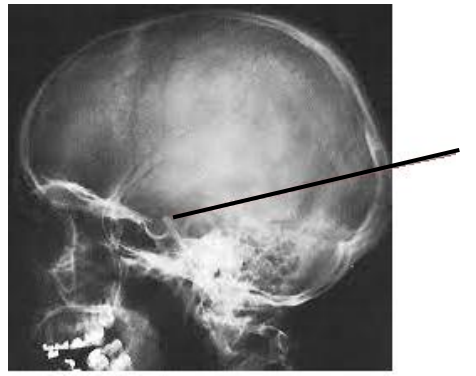

A imagem radiológica abaixo aponta pela seta a estrutura anatômica denominada:

Fonte: http://anatpat.unicamp.br/rpgcraniofar2.html